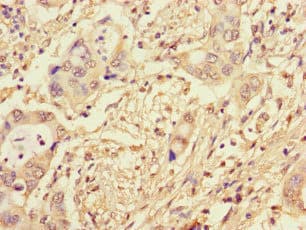

Anti-NCM antibody(ab234709)

Rabbit Polyclonal NCM antibody. Suitable for IHC-P, ICC/IF and reacts with Human samples. Immunogen corresponding to Recombinant Fragment Protein within Human Pre-mRNA-splicing factor CWC22 homolog aa 350-650.

Applications ICC/IF, IHC-P